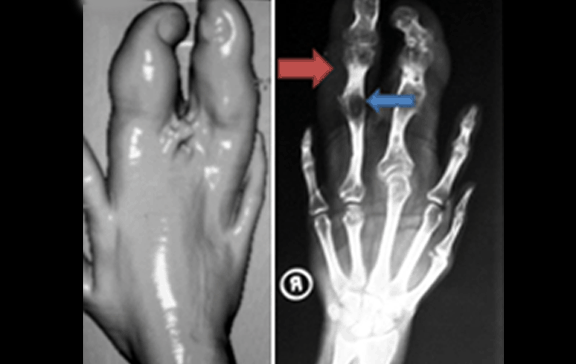

Volume rendering technique image showing gross enlargement of middle and ring figures of right hand, Plain radiographs right hand anteroposterior and lateral views showing enlargement of 3rd and 4th fingers with overgrowth of soft tissue as well as bony metacarpals and phalanges. There is predominantly increased lucency in soft tissue compartment of affected fingers suggestive of fat (red arrows) and secondary degenerative changes with partial ankylosis at interphalangeal joints (blue arrows) (Page 496)